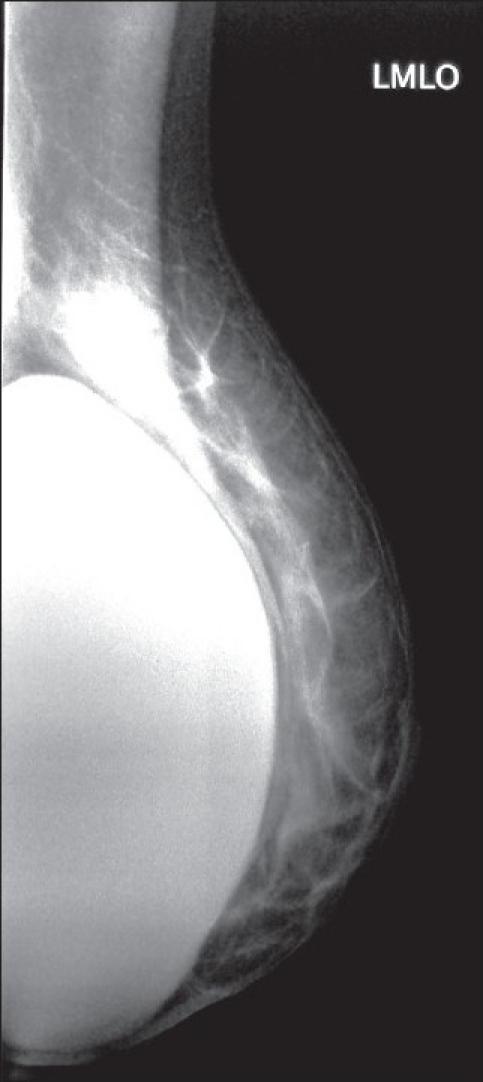

We report a case involving a 45-year-old woman, who presented with an axillary mass 10 years after bilateral cosmetic augmentation mammaplasty. A lump was detected in the left axilla, and subsequent mammography and magnetic resonance imaging demonstrated intracapsular rupture of the left breast prosthesis. An excisional biopsy of the left axillary lesion and replacement of the ruptured implant was performed. Histological analysis showed that the axillary lump was lymph nodes containing large amounts of silicone. Silicone lymphadenopathy is an obscure complication of procedures involving the use of silicone. It is thought to occur following the transit of silicone droplets from breast implants to lymph nodes by macrophages and should always be considered as a differential diagnosis in patients in whom silicone prostheses are present.

我们报告了一例病例,患者为一名45岁女性,在双侧隆胸整形术后10年出现腋窝肿块。在左腋窝发现一个肿块,随后的乳房X线摄影和磁共振成像显示左乳房假体包膜内破裂。对左腋窝病变进行了切除活检,并更换了破裂的植入物。组织学分析表明,腋窝肿块是含有大量硅胶的淋巴结。硅胶淋巴结病是涉及使用硅胶的手术中一种罕见的并发症。它被认为是在硅胶滴通过巨噬细胞从乳房植入物转移到淋巴结后发生的,对于存在硅胶假体的患者,应始终将其视为鉴别诊断。